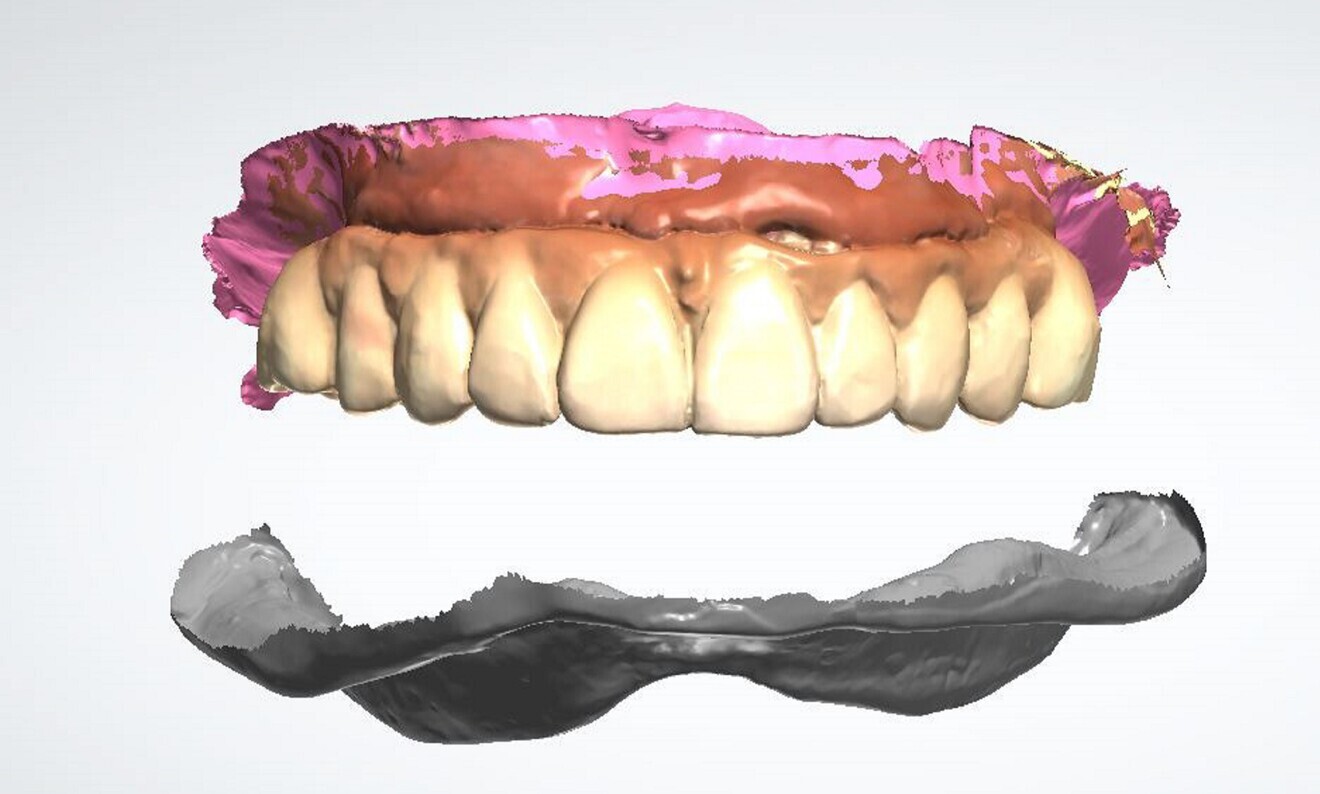

Fig. 4: Intra-oral scans of the maxillary and mandibular arches.

Fig. 5: Virtual removal of the maxillary prosthesis in exocad software.